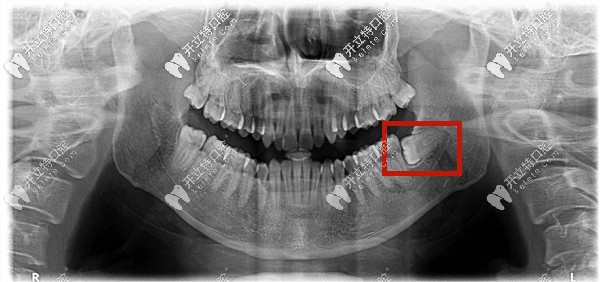

什么是低位阻生齒——就是下頜的阻生智齒的牙冠部位低于前面牙齒的牙頸部以下。

低位水平阻生齒圖片

下頜低位阻生智齒圖片

低位阻生齒——就是牙的高處部位低于第二磨牙的牙頸部,它可以是近中低位,垂直低位,遠(yuǎn)中低位等,也有可能牙全部被包埋在牙骨內(nèi),所以又稱(chēng)之為骨埋伏阻生智齒。

這種情況下的智齒一般從口中看不到,需要拍片才能確定。